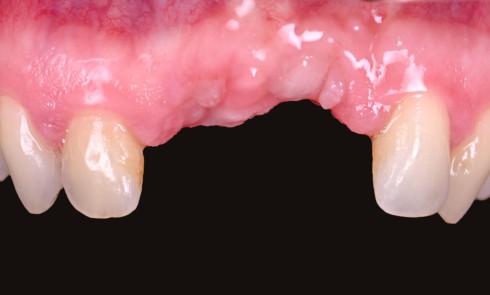

Anamnèse Une patiente de 29 ans, sans antécédent médical rapporté et non-fumeuse, consulte pour une inflammation gingivale persistante, malgré plusieurs...